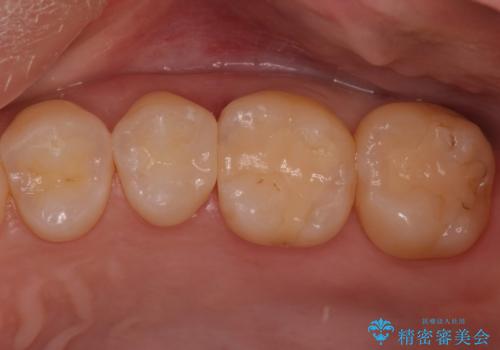

![[e-maxインレー] 矯正治療前の虫歯治療の症例 治療後](https://seimitsushinbi.jp/wp/wp-content/uploads/2023/08/IMG_2869-1-500x350.jpg?v=1691812292)